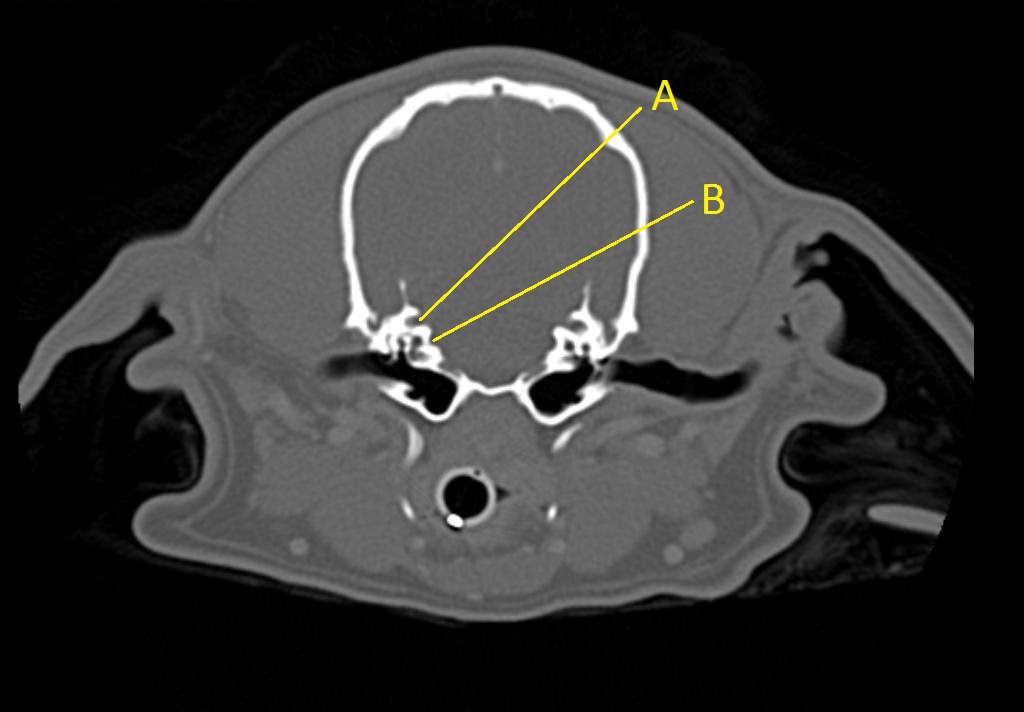

Q. Identify the structures labeled below:

A.

A. cerebellar recess

B. internal acoustic meatus